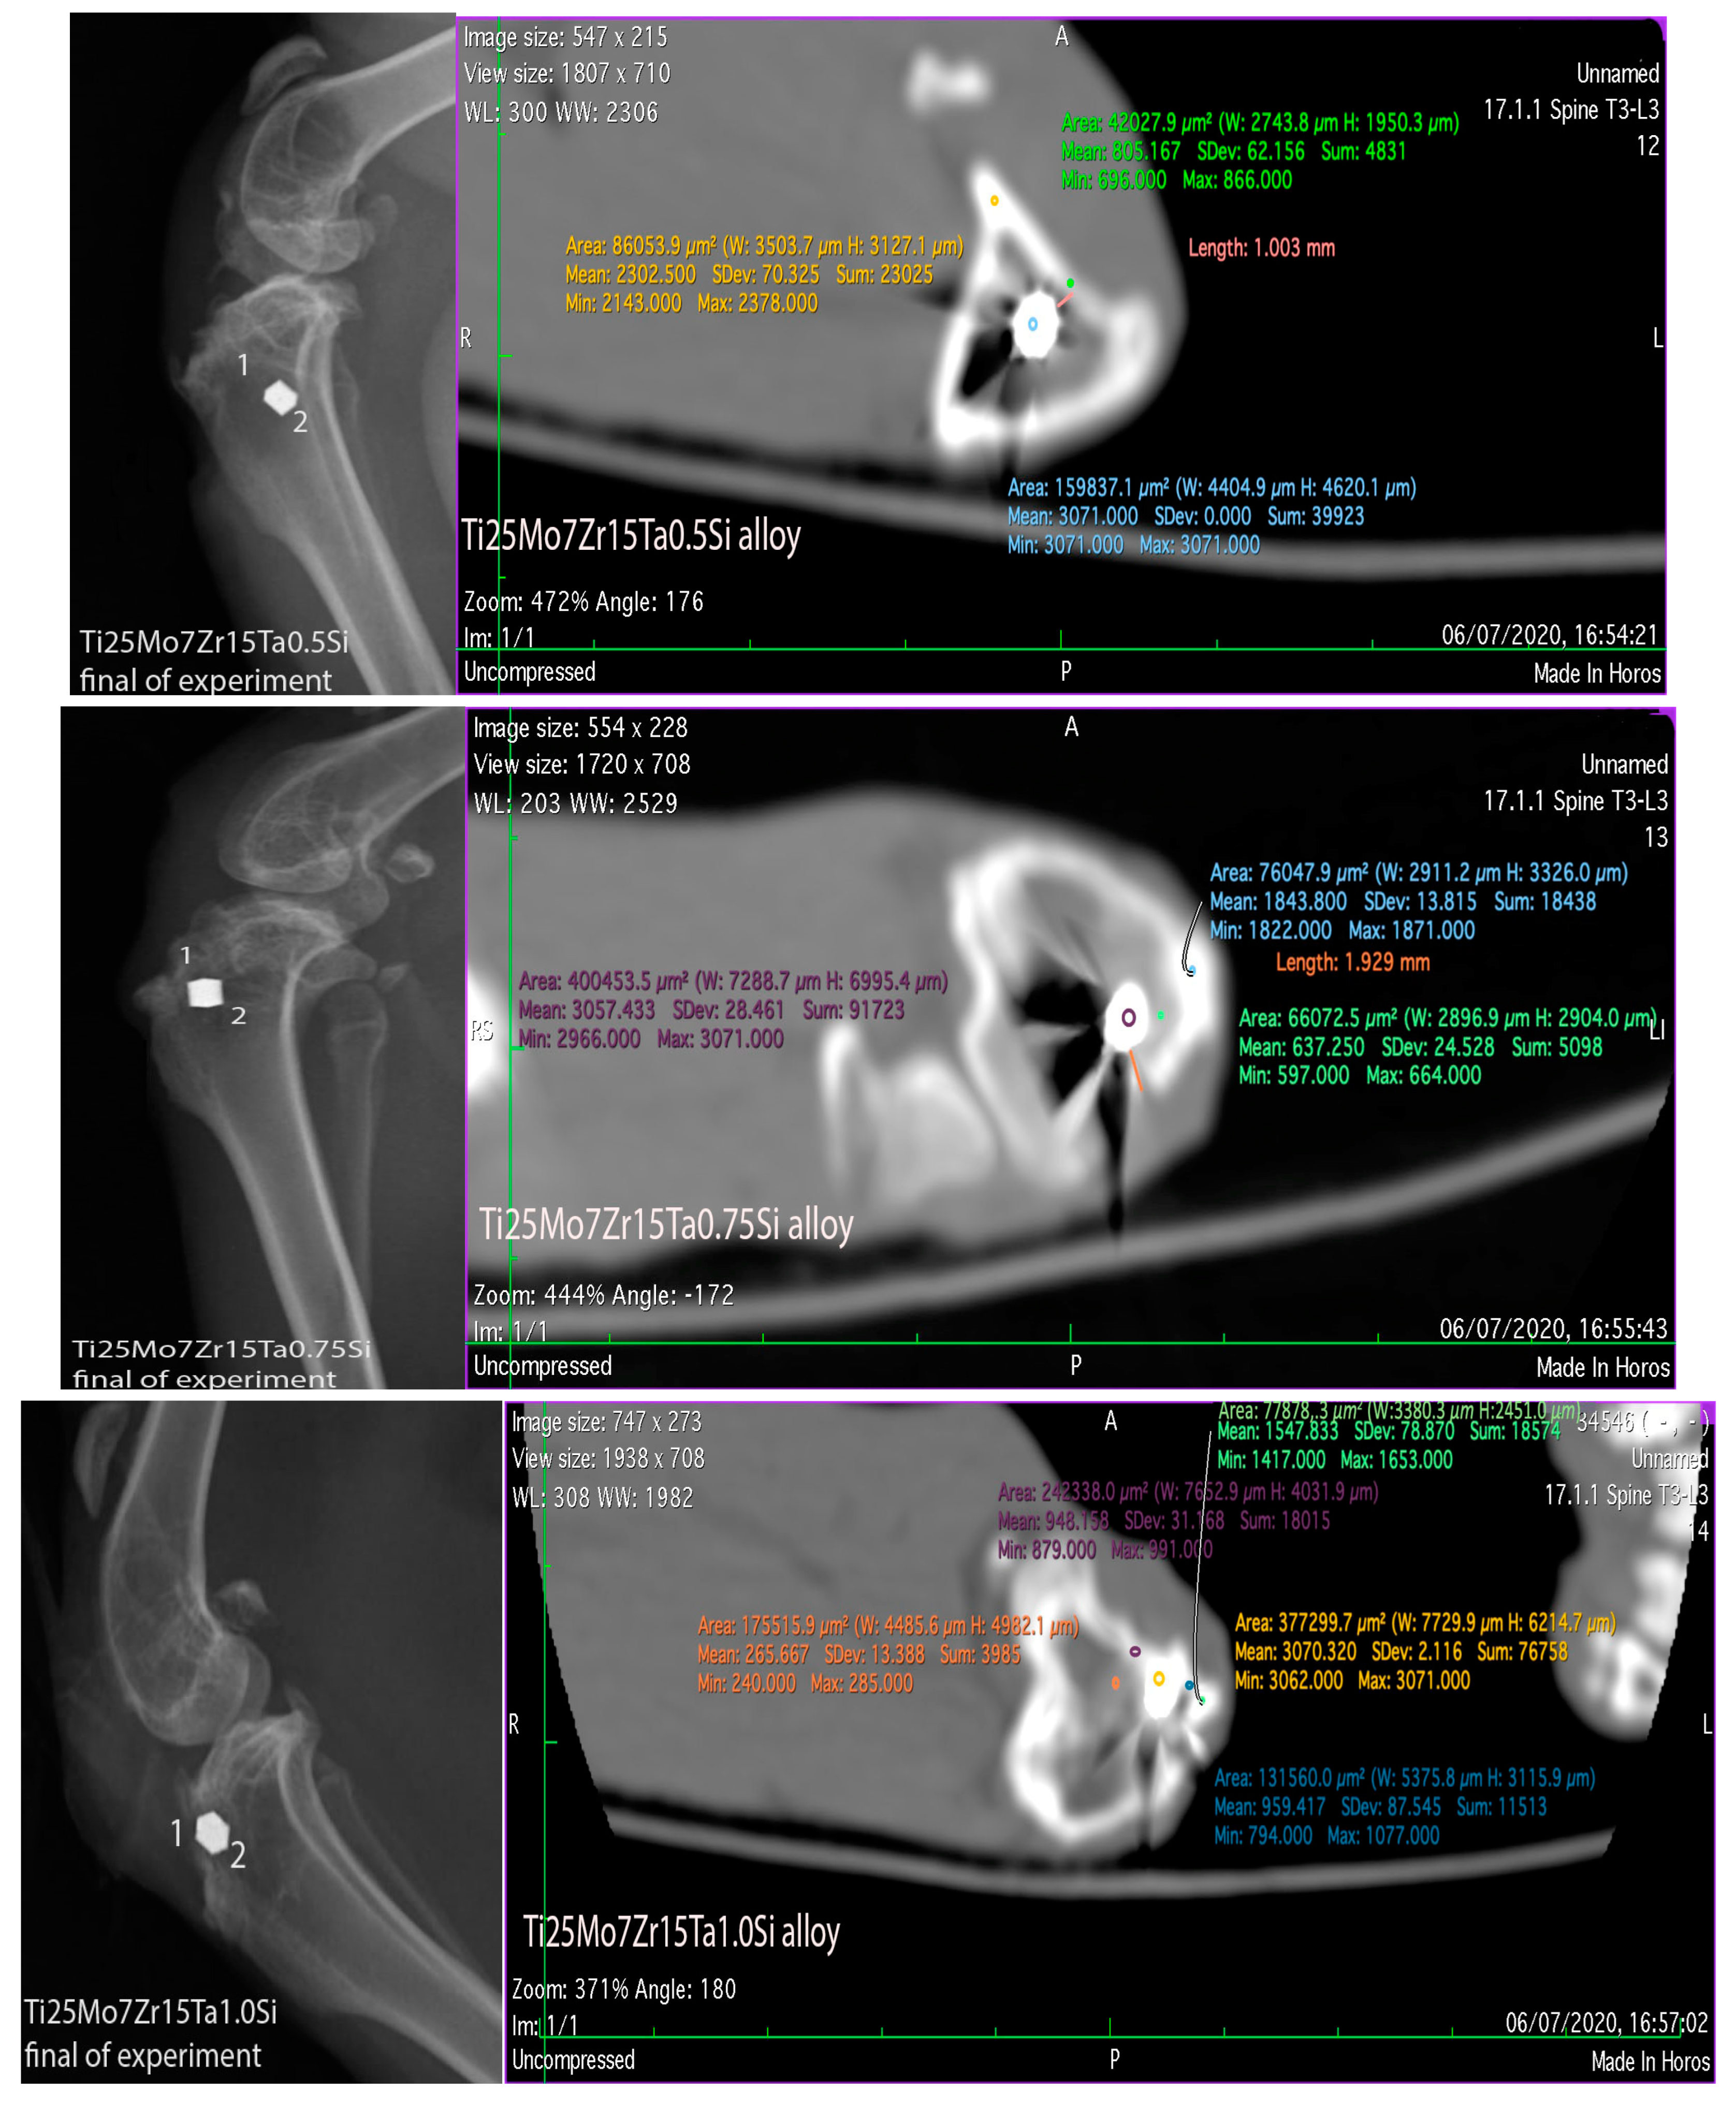

3.3. Interpretation of Results, Radiographs and Micrographs